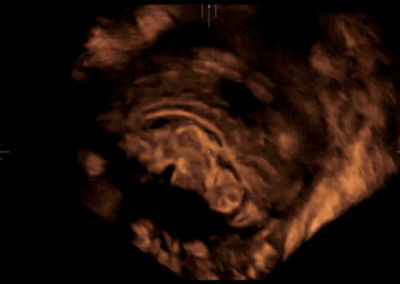

NueWa i9

El Nuewa I9, diseñado exclusivamente para mujeres y atención médica neonatal, brinda una experiencia innovadora integral. Estas innovaciones se desarrollan sobre la base de conocimientos profundos en escenarios clínicos complejos, para proporcionar respuestas precisas y oportunas, una gran eficiencia y una experiencia de usuario extraordinaria. •

- Diseño del panel de control inteligente y específico para exámenes clínicos con teclas especiales de tinta electrónica

- Diseño innovador con diseño adaptable para diferentes situaciones clínicas

RESONA i9

Resona I9 es un sistema de ecografía de aplicación general con características notablemente innovadoras. Estas innovaciones se desarrollan sobre la base de conocimientos profundos en situaciones clínicas complejas, para proporcionar respuestas precisas y oportunas, una gran eficiencia y una notable experiencia de usuario.